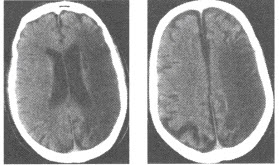

患者,男,31岁。车祸伤致昏迷半小时急诊入院。

第1题,共2个问题

(多选题)下图CT显示的疾病有()

A:硬膜外血肿

B:硬膜下血肿

C:蛛网膜下腔出血

D:脑疝

E:颅内出血

F:颅骨骨折

第2题,共2个问题

(多选题)硬膜下血肿的CT征象为()

A:亚急性期表现为高、低、等混杂密度

B:慢性为颅板下新月形高密度影

C:常合并脑挫裂伤,占位效应明显

D:慢性硬膜下血肿可形成盔甲脑

E:少部分慢性硬膜下血肿可形成分隔

F:急性硬膜下血肿通常合并硬膜外血肿